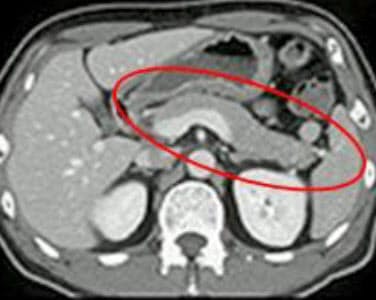

大津赤十字病院では膵臓疾患に対しては, multi-detector CT を使用し,動脈早期相,動脈後期相,平衡相の 3 phase の造影画像が得られる ダイナミック CT 撮影 を基本にしている. FDG-PET. )-1000 -800 -600 -400 -0 0 0 400 600 800 +1000 水 脂肪組織 軟部組織 骨、石灰化 空気、ガス CT画像は各組織のCT値分布図である! CT値(単位:Hounsfield Unit) 水 :0 空気:-1000. 腹部造影ctの横断像です。 左から経時的に提示しています。 膵臓は腫大し、周囲に脂肪織濃度上昇および液体貯留、腹膜の肥厚を認めています。 急性膵炎のct画像所見です。 少し時間が経過した、右側の画像では、膵臓の腹側に巨大な液貯留を認めています。.